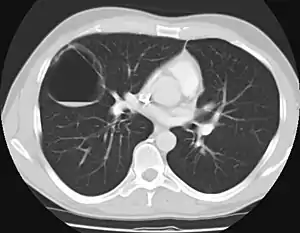

Imaging

The earliest point at which a CPAM can be detected is by prenatal ultrasound. The classic description is of an echogenic lung mass that gradually disappears over subsequent ultrasounds. The disappearance is due to the malformation becoming filled with fluid over the course of the gestation, allowing the ultrasound waves to penetrate it more easily and rendering it invisible on sonographic imaging. When a CPAM is rapidly growing, either solid or with a dominant cyst, they have a higher incidence of developing venous outflow obstruction, cardiac failure and ultimately hydrops fetalis. If hydrops is not present, the fetus has a 95% chance of survival. When hydrops is present, risk of fetal demise is much greater without in utero surgery to correct the pathophysiology. The greatest period of growth is during the end of the second trimester, between 20–26 weeks.

A measure of mass volume divided by head circumference, termed cystic adenomatoid malformation volume ratio (CVR) has been developed to predict the risk of hydrops. The lung mass volume is determined using the formula (length × width × anteroposterior diameter ÷ 2), divided by head circumference. With a CVR greater than 1.6 being considered high risk. Fetuses with a CVR less than 1.6 and without a dominant cyst have less than a 3% risk of hydrops. After delivery, if the patient is symptomatic, resection is mandated. If the infant is asymptomatic, the need for resection is a subject of debate, though it is usually recommended. Development of recurrent infections, rhabdomyosarcoma, adenocarcinomas in situ within the lung malformation have been reported.[4]

In most cases, a fetus with CPAM is closely monitored during pregnancy and the CPAM is removed via surgery after birth.[5] Most babies with a CPAM are born without complication and are monitored during the first few months. Many patients have surgery, typically before their first birthday, because of the risk of recurrent lung infections associated with CPAMs. Some pediatric surgeons can safely remove these lesions using very tiny incisions using minimally invasive surgical techniques (thoracoscopy). However, some CPAM patients live a full life without any complication or incident. It is hypothesized that there are thousands of people living with an undetected CPAM. Through ultrasound testing employed in recent years, many more patients are aware that they live with this condition. Rarely, long standing CPAMs have been reported to become cancerous.